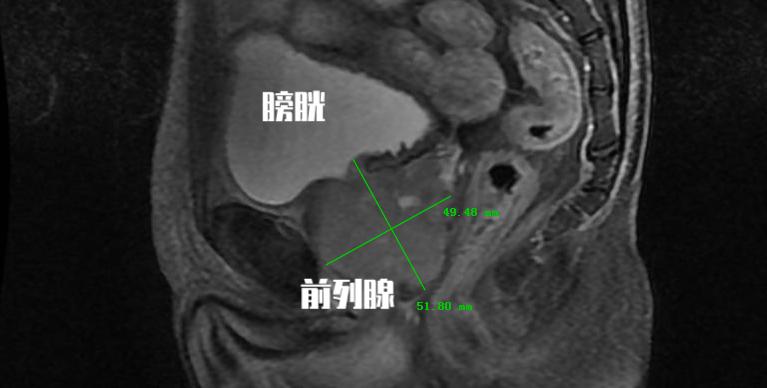

膀胱逼尿肌功能减退,膀胱功能低下不能手术治疗,或经手术治疗后功能仍不能使膀胱排空仍存在较多残余尿的前列腺增生患者,可以中医药疗法为主导。

这部分患者多是已经处 于膀胱的失代偿期 ,划归到前列腺增生的病程中就是已经 处于中晚期的意思 ,这部分患者即使接受手术治疗, 由于膀胱功能已经受损,解除尿路梗阻后仍不能获得有效疗效。 部分研究发现中医药治疗可有效改善患者膀胱活动低下态势, 提高膀胱收缩力 ,认为术后排尿困难的患者可以经过中医药治疗,可以获得良好的临床疗效。